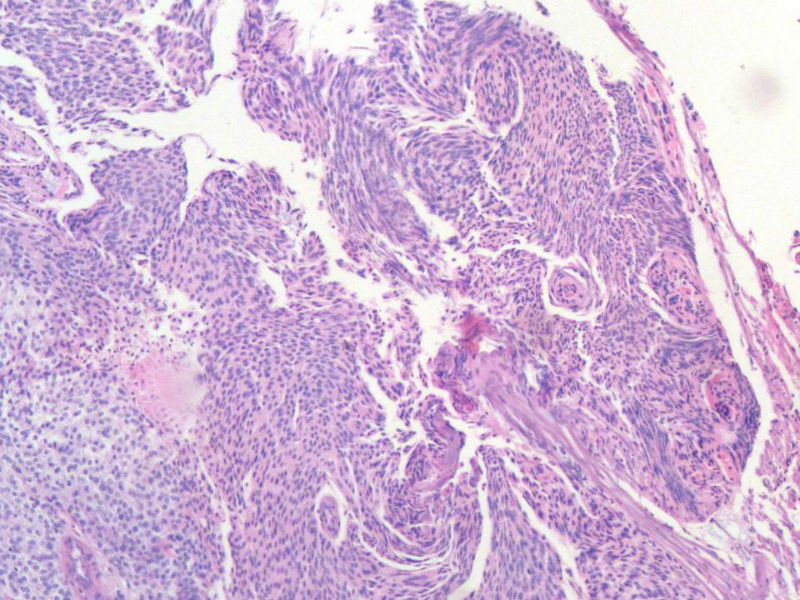

女,64岁,头晕半月,CT检查颅内左颞叶占位,侵犯颅骨和颞肌,手术切除肿物。肉眼,灰白色结节状肿物,3X3X2厘米,边界不清,切面灰黄色,质软。

特别提示:手术前曾做过介入肿瘤栓塞。镜下核分裂15/HP。脑左颞部占位图1

梭形细胞与上皮样漩涡状结构,富于细胞,见个别沙砾体,并见肿瘤性坏死。颅骨及其横纹肌等软组织内见肿瘤呈侵袭性生长。但细胞异型性不是很大。鉴别:

1)恶性脑膜瘤

2)非典型性脑膜瘤

由于非典型性脑膜瘤也可以发生地图状坏死,甚至侵袭性生长。需要计数核分裂数/10HPF,以资鉴别诊断。